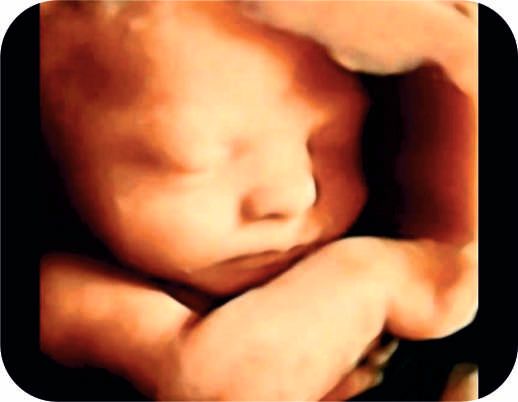

Photo Gallery CT Machine ICU Modular OT Private Ward General Ward USG Fetal 3D Fetal Intervention 1 Fetal Intervention 2